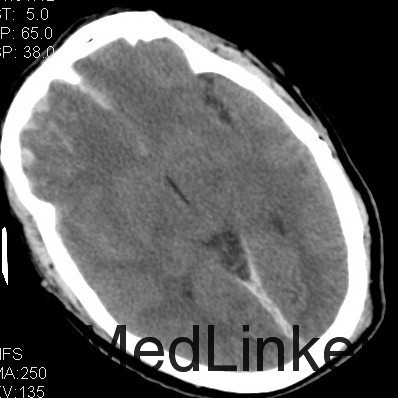

主诉:头部外伤7小时 病史:患者于7小时余前不慎从2米高处坠落,头部着地,并昏迷,左侧外耳道出血,无呕吐,无肢体抽搐,无明显头晕及头痛,无胸闷心悸,呼120入我院急诊诊治,行头颅CT提示有:头部螺旋CT平扫:1、蛛网膜下腔出血;大脑镰硬膜下出血;双侧额叶脑挫伤;脑肿胀。2、左侧枕骨骨折;左侧顶枕部头皮下血肿。3、双侧筛窦炎症。入急诊后患者神志转清,在急诊给予止血、脱水等治疗,4小时后复查头颅CT提示血肿增大及挫裂伤较前明显加重,为进一步治疗,收入我科。患者起病前,精神食欲可,二便可,体重无明显变化。

查体:神志昏睡,间断烦躁,刺激可睁眼,无对答,查体不合作,双侧瞳孔等大等圆,直径3mm,对光反应尚可,枕部可见隐约血肿,约1*1cm,左耳见血性液体流出。深浅感觉查体及腱反射查体不合作,双侧病理征未引出。格拉斯哥评分9分。 4:辅助检查:头部螺旋CT平扫(套:1、蛛网膜下腔出血;大脑镰硬膜下出血;双侧额叶脑挫伤;脑肿胀。2、左侧枕骨骨折;左侧顶枕部头皮下血肿。3、双侧筛窦炎症。颈椎螺旋CT平扫+三维:寰椎与枢椎齿状突之间高密度影,考虑撕脱骨折与钙化灶鉴别,建议复查或MRI进一步检查。

诊断:1、双侧额挫裂伤; 2、大脑镰、右侧额颞硬膜下出血;3、右额颞脑出血; 4、左枕骨骨折; 5、中枢神经系统感染 主要经过:入院后完善术前相关检查,行右侧额颞脑挫裂伤清除+去骨瓣减压+颅内压探头置入术;后行左侧额叶血肿清除+额颞顶去骨瓣减压术,术后予以抗感染、营养神经、改善循环、化痰、护胃、抗癫痫及营养支持治疗。 术后复查CT:双侧额颞顶骨局部缺如;左侧枕骨不连。 双侧额颞顶部皮下软组织稍肿胀。双侧额叶软化灶;右侧额颞部硬膜下及大脑纵裂池积液;右侧额颞部少量积气